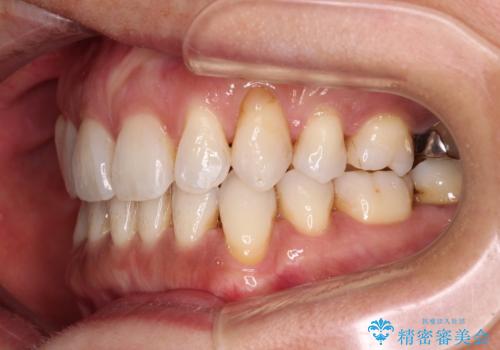

抜歯矯正の後戻りをインビザライン・ライトで解消

- 下顎前歯を中心に、以前行った矯正治療の後戻りが気になるとのことで来院された患者様です。

後戻りは軽度であったため、インビザライン・ライトにて治療を行うこととしました。

矯正治療後は、再度後戻りすることを極力回避するために、下顎前歯の舌側を細いワイヤーを用いて保定することとしました。